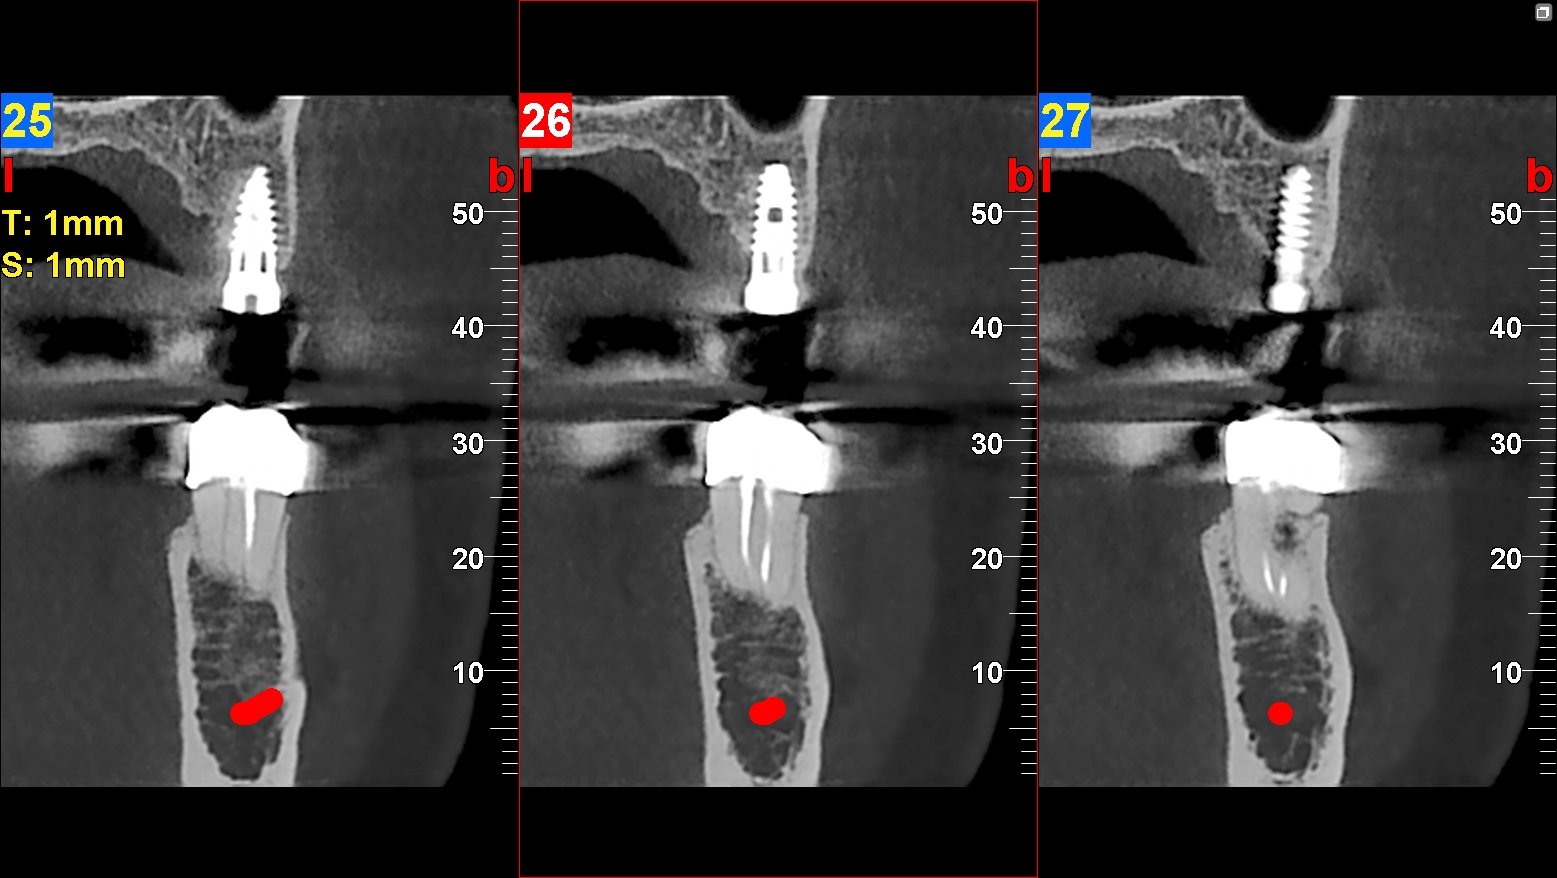

Una de las principales ventajas del TAC macizofacial es su capacidad para proporcionar imágenes tridimensionales que permiten una evaluación más completa de la anatomía dental. Esto es especialmente beneficioso en casos donde se requiere una visualización detallada de estructuras complejas, como los senos paranasales o las raíces dentales. La información obtenida a través del TAC puede ser decisiva para establecer un diagnóstico correcto y para elegir el tratamiento más adecuado.

La precisión en el diagnóstico dental es fundamental para garantizar tratamientos efectivos y minimizar complicaciones. El TAC macizofacial ofrece un nivel de detalle que supera al de las radiografías convencionales, permitiendo a los profesionales identificar problemas específicos con mayor facilidad. Por ejemplo, en casos de malformaciones congénitas o lesiones traumáticas, el TAC puede proporcionar información crucial sobre la ubicación y extensión del problema.

El TAC macizofacial desempeña un papel esencial en la planificación de tratamientos dentales complejos. Por ejemplo, en la colocación de implantes dentales, es crucial conocer la densidad ósea y la ubicación exacta de las estructuras anatómicas cercanas, como nervios y senos maxilares. Con las imágenes obtenidas a través del TAC, los odontólogos pueden diseñar un plan quirúrgico personalizado que minimice riesgos y maximice la eficacia del tratamiento.

Además, esta tecnología permite simular procedimientos quirúrgicos antes de realizarlos en el paciente. Los odontólogos pueden utilizar software especializado para crear modelos tridimensionales basados en las imágenes del TAC, lo que les permite practicar y prever posibles complicaciones antes de llevar a cabo la intervención real.Esta planificación meticulosa no solo mejora los resultados clínicos, sino que también aumenta la confianza tanto del profesional como del paciente.

El examen de tac macizofacial proporciona imágenes detalladas en 3D que permiten una evaluación precisa de la estructura ósea, la ubicación de los dientes, la calidad del hueso para implantes, y la detección de patologías o lesiones.